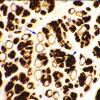

PERIPHERAL NEUROPATHY

1 NORMAL NERVE ANATOMY

2 Normal IHC